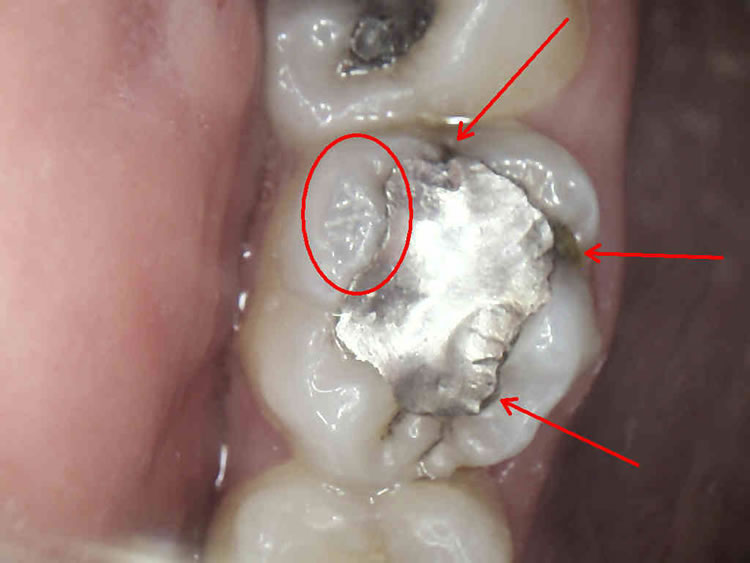

Svima dobro poznati, sivi, amalgamski ispuni, danas se iz zdravstvenih i estetskih razloga zamjenjuju estetskim, kompozitnim ispunima.

Naša su iskustva u praksi da redovno, ispod amalgamskog ispuna, u toku sanacije zuba pronalazimo karijes. Obrazloženje je u činjenici da se amalgam kao materijal za ispun s vremenom skvrčava i time stvara pukotinu između sebe i stjenke zuba. To naravno dovodi do prodora bakterija karijesa u kavitet na zubu a time i kvarenja zuba.

Estetski ( bijeli ) materijali ne mijenjaju volumen tijekom vremena. Dakle, nema pukotine, nema prodora bakterija i nema kvarenja zuba.

Postavljanjem estetskog materijala postižemo kvalitetnu rekonstrukciju zubnog tkiva i potpuno prirodan izgled za razliku od ( sivog, metalnog ) amalgamskog ispuna.

Za izradu estetskog ispuna potrebno je odstraniti samo bolestan dio zuba za razliku od amalgamskog ispuna za koji je bilo potrebno odstraniti i dio zdravog zubnog tkiva zbog držanja amalgama u zubu.